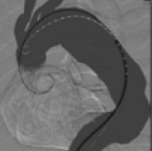

EVAR MODULE (AAA): Dual Access!

PROcedure Rehearsal Studio Ready!

The module consists of 6 different cases, designed to enable comprehensive hands on training on Endovascular Abdominal Aortic Aneurysm Repair using graft systems and touch-up ballooning.

The library of patients feature anatomical variations such as: abdominal aneurysm enlargements, different sizes of aortic neck, neck angulations, different positions of renal arteries and ruptured abdominal aorta.

Complications include stent graft migration and type I and III endoleaks.

UNIQUE! Includes a self-guided tutorial case that guides the trainee through the procedure steps and allows skipping steps. ANGIO MENTOR EXCLUSIVE!